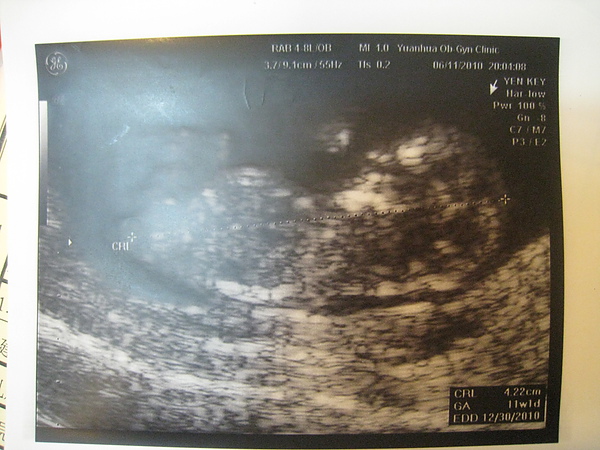

今天baby的周數已經算是邁向11w了~

後來醫生說他今天順便看一下頸部透明帶的厚度

醫生比較好量頸部的透明帶

不過醫生覺得好像有厚了一點

醫生說現在的厚度最好是2mm以下比較好

我的baby的數據在1.9mm~2mm之間游走